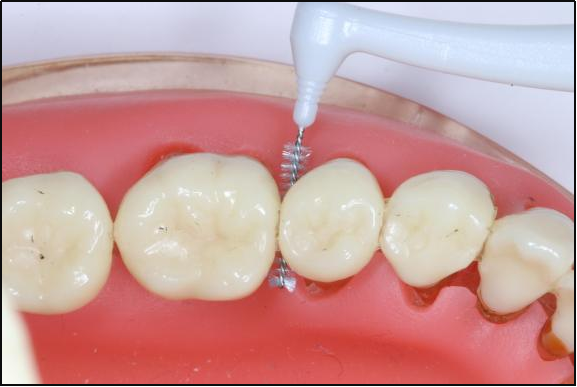

牙石和牙菌斑:隐藏的填充物

长期的牙菌斑和牙石积累不仅是牙周病的罪魁祸首,还在一定程度上“填充”了你的牙缝。当这些牙石被清理掉后,原本被牙石填充的空间就会显露出来,这就让你觉得牙缝变大了。

治疗前

治疗后

牙结石